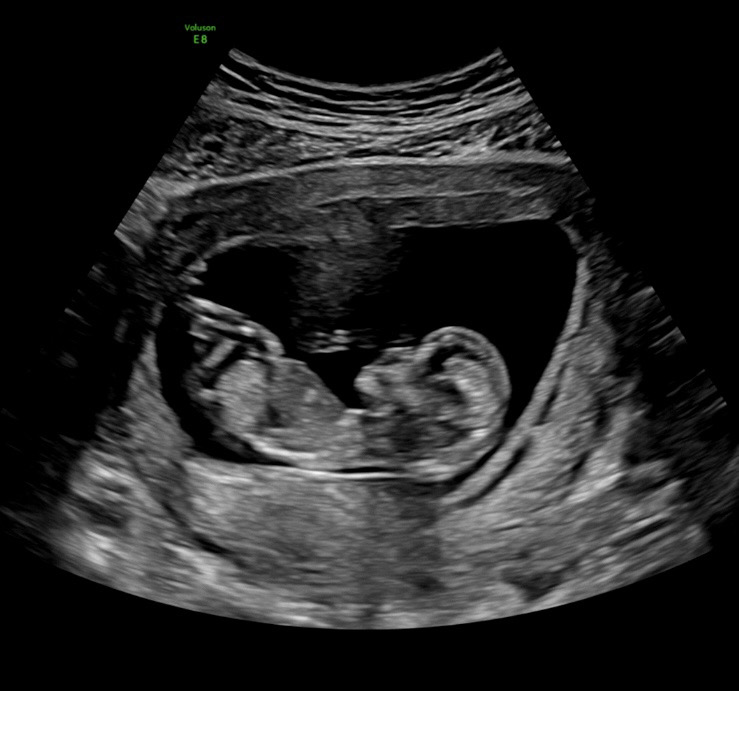

딸일가요? 아들일가요?

각도법고수님들 12주에요 ~~~~ 어떻게보이세용?

튀어나온거로 봐서는 아들같아요!